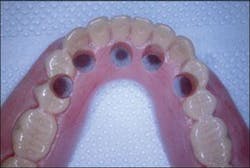

Figure 9 - Preparation of the prosthesis to pick up the temporary cylinders and convert the interim denture into the fixed provisional restoration

Temporary cylinders were then placed on the multiunit abutments (Figure 10) and verified that they fit through the holes in the denture. The occlusion was verified and adjusted, and the cylinders were then luted to the prosthesis with cold-cure resin (Figure 11). The temporary cylinders were then unscrewed and the prosthesis was removed from the oral cavity along with the luted cylinders (Figure 12).

In the laboratory, tissue-color cold-cure methylmethacrylate filled in the voids around the temporary cylinders, and the undersurface of the prosthesis was filled in to form a convex, cleansable surface. The prosthesis was trimmed, removing the buccal and lingual flanges and shortening the dentition to first-molar occlusion (Figure 13). The prosthesis was then polished after placing polishing protectors on the undersurface of the temporary cylinders.